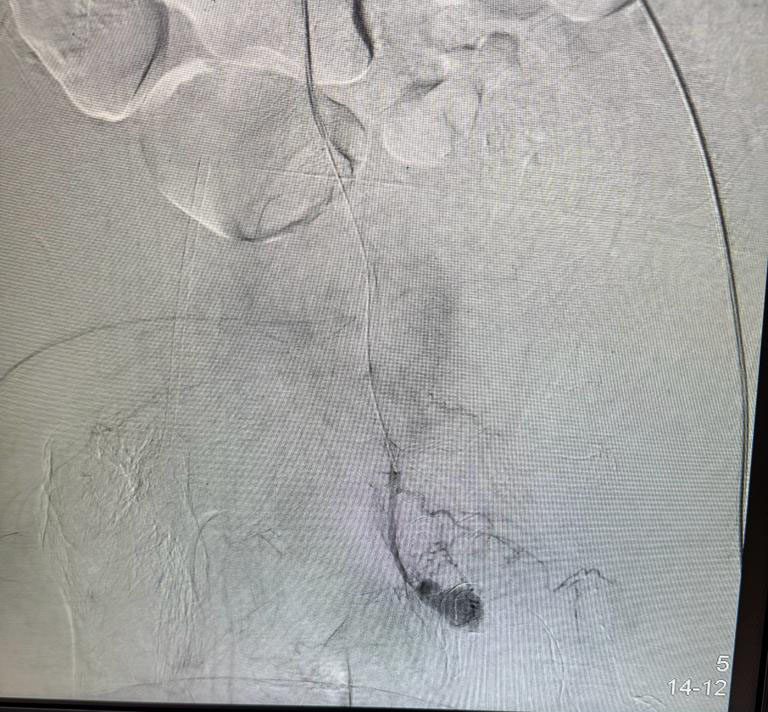

Endovascular Treatment Of Gangrene ( Multi Level Correction)

Vascular embolization of arteriovenous malformation